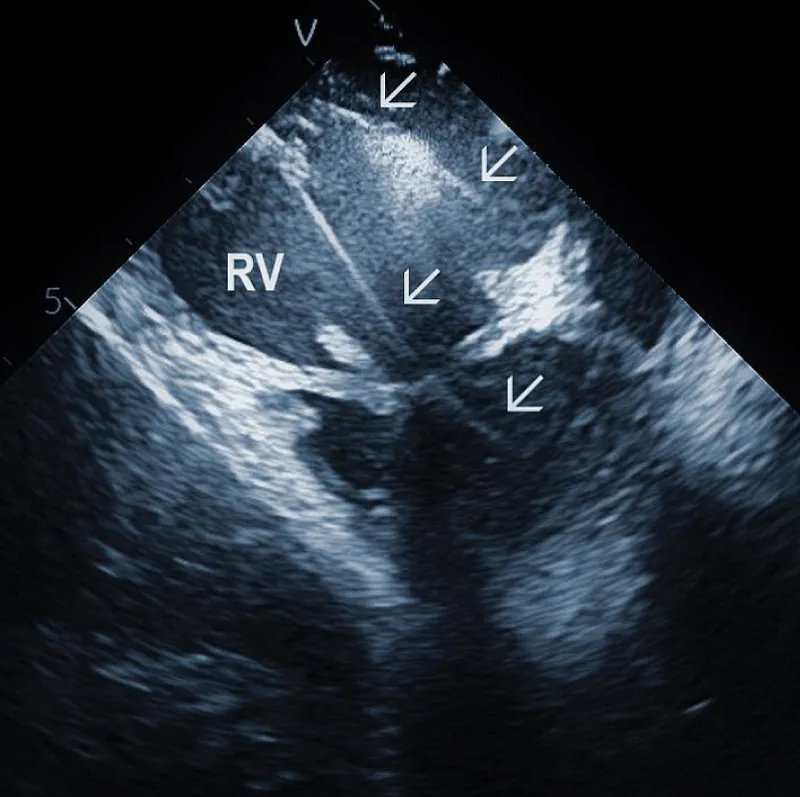

Areas of fibrous adherence: Areas of fibrous adherences or attachments (i.e., scar tissue) can be visualized as echo-dense structures along the lead course (Figure 3A). Multiple leads are usually attached by fibrous tissue together (Figure 3B). The location of fibrous adherence can be anywhere in the course of the lead [7,10]. In a study by Bongiorni, et al. [7], scar tissue was noted by ICE in the subclavian vein, innominate vein, and the right ventricle in about 80%, 68%, and 68% of cases, respectively. Sadek, et al. [10] described attachments less frequently – only in 18/50 pts (36%), predominantly intracardiac. Anecdotal cases were reported on specific locations of adhesions, such as a vulnerable “stalk” attaching the papillary muscle to the RV endocardium [18]. Notably, the fibrous attachment presence correlated with the extraction procedure’s difficulty. These patients were more likely to have a “complex” extraction procedure. Subjects who did not have evidence of lead attachment were less likely to require the advancement of the extraction sheaths past the superior vena cava and less likely to require advanced extraction tools such as snares.

Figure 3B: A convolute of 2 leads attached together with fibrous tissue at the level of tricuspid valve (arrows). RA: Right Atrium; RV: Right Ventricle.